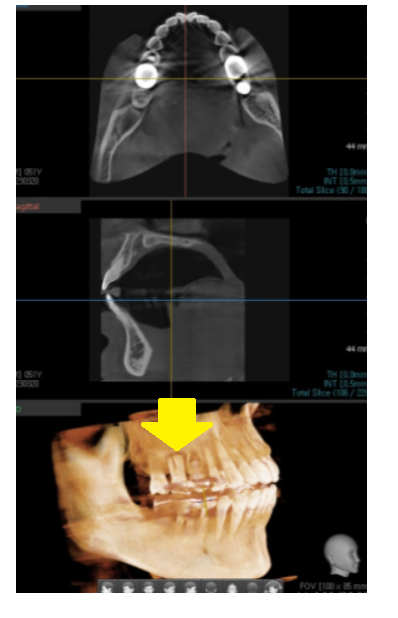

23.03.29

뼈가 너무 없어서

이대로라면 고덕동 임플란트가 어려웠습니다.

발치 후 뼈이식을 1차적으로 진행

뼈가 찰때까지 기다렸는데요.